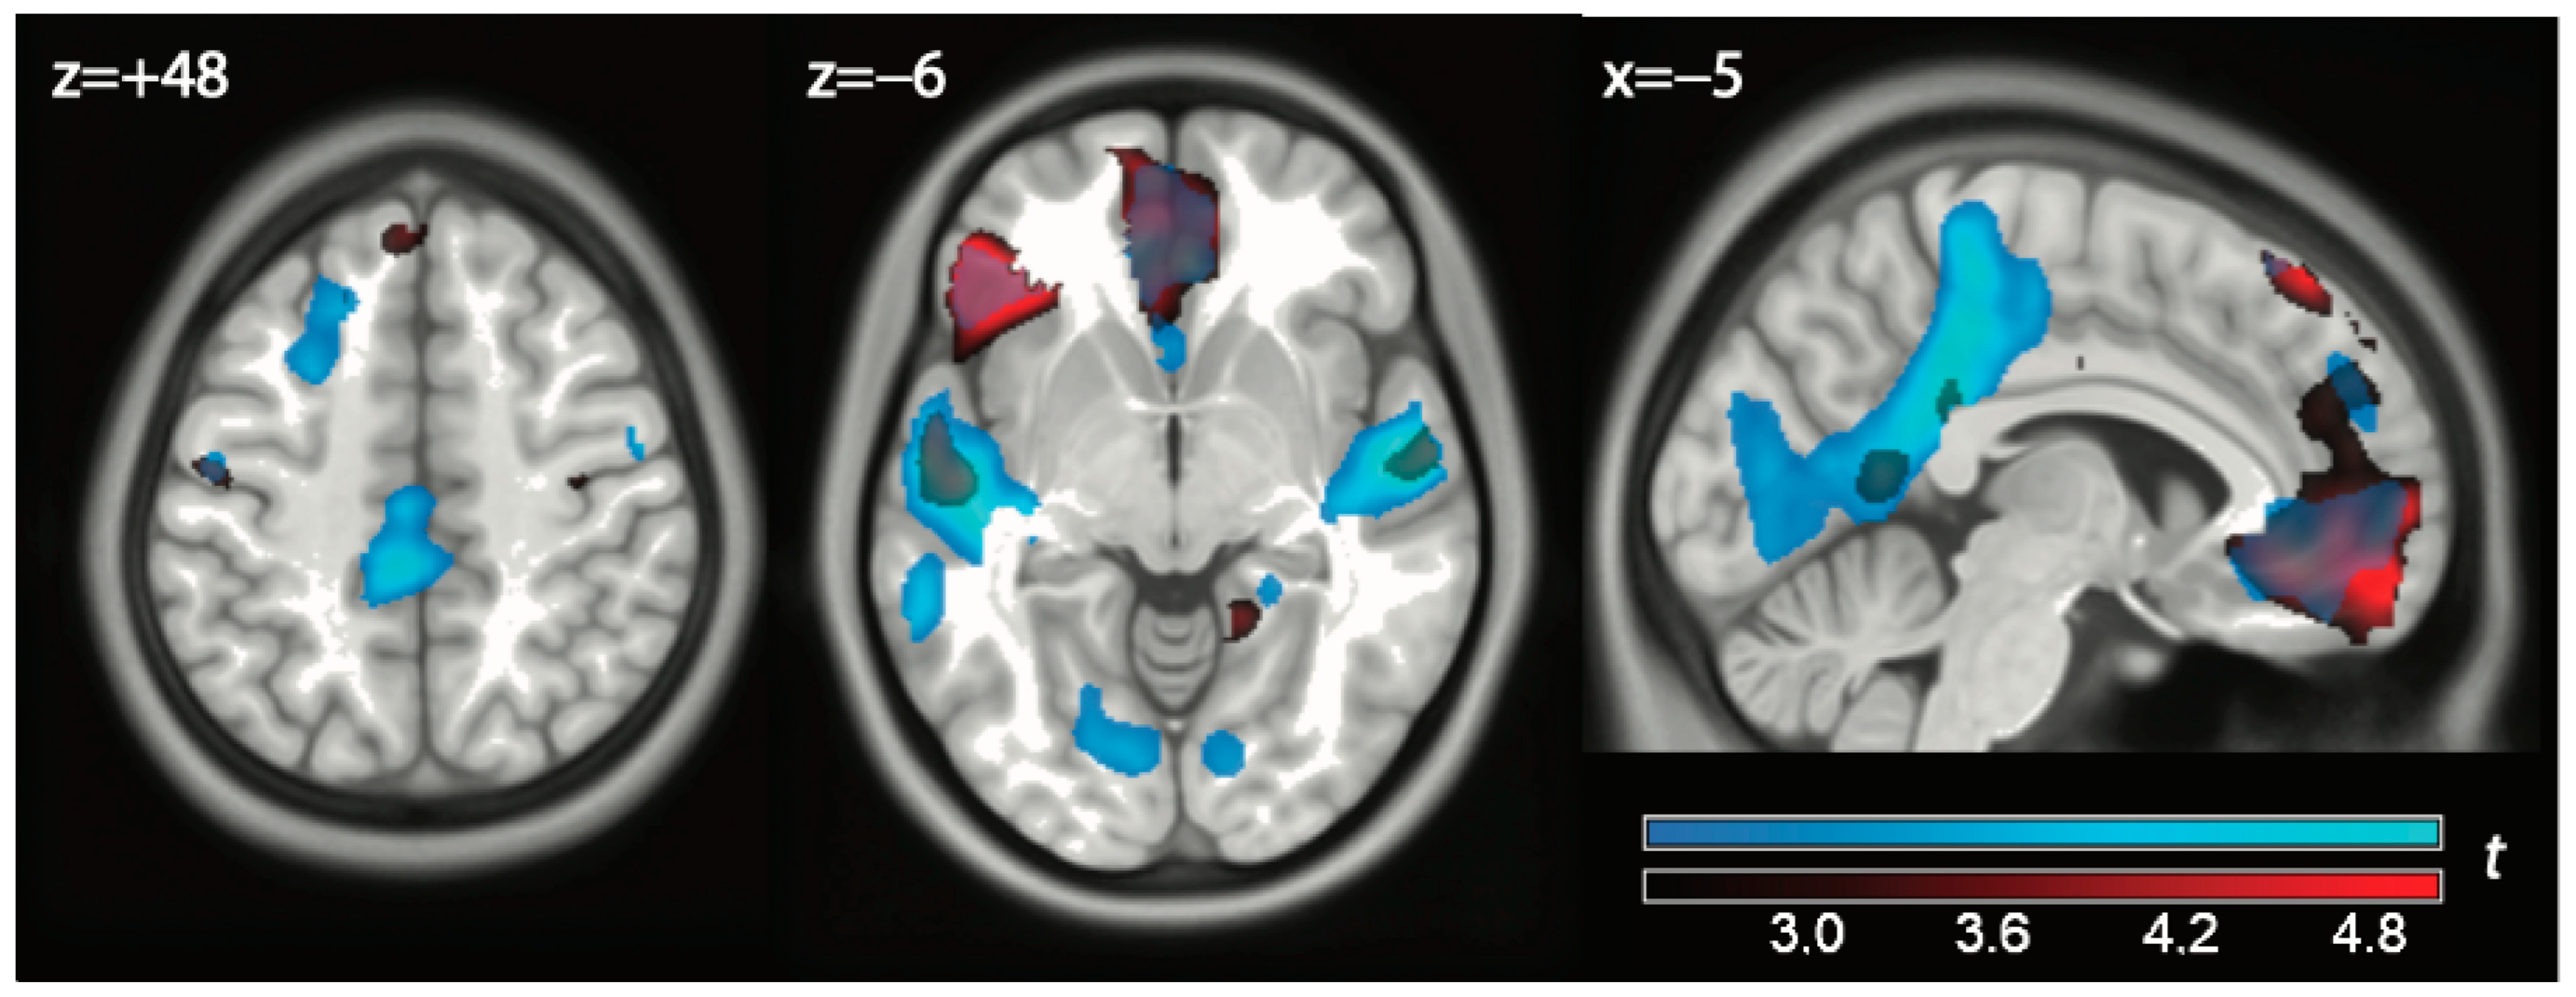

| Exclusion vs. play | |||||||

| 1 | Left Inferior Frontal Gyrus (BA 47) | −50 38 −8 | 7.088 | <0.0001 | 0.002 | 1326 | 0.002 |

| <0.001 * | 802 | <0.001 * | |||||

| Left Inferior Frontal Gyrus (BA 47) | −36 30 −4 | 6.091 | <0.0001 | 0.009 | |||

| <0.001 * | |||||||

| Left Inferior Frontal Gyrus (BA 47) | −48 28 −6 | 5.748 | <0.0001 | 0.021 | |||

| Left Sup Temporal Gyrus (BA 38) | −48 12 −28 | 4.900 | <0.0001 | 0.116 | |||

| Left Inferior Frontal Gyrus (BA 47) | −50 28 10 | 4.815 | <0.0001 | 0.133 | |||

| Left Temporal Pole (BA 20) | −40 6 −46 | 4.129 | 0.0002 | 0.385 | |||

| 2 | Left Medial Frontal Gyrus (BA 11) | −6 60 −14 | 5.839 | <0.0001 | 0.018 | 1031 | 0.004 |

| <0.001 * | 919 | <0.001 * | |||||

| Left Sup Frontal Gyrus (BA 10) | −12 64 2 | 5.405 | <0.0001 | 0.043 | |||

| 0.001 * | |||||||

| Left Medial Frontal Gyrus (BA 11) | −2 38 −12 | 4.916 | <0.0001 | 0.112 | |||

| 0.002 * | |||||||

| Left Sup Frontal Gyrus (BA 10) | −4 64 2 | 4.627 | <0.0001 | 0.187 | |||

| 0.005 * | |||||||

| Right Med Frontal Gyrus (BA 11) | 8 46 −8 | 3.873 | 0.0004 | 0.525 | |||

| Play vs. exclusion | |||||||

| 3 | Left Mid Temporal Gyrus (BA 37) | −46 −64 4 | −9.968 | <0.0001 | 0.000 | 1551 | 0.002 |

| Left Fusiform Gyrus (BA 37) | −42 −50 −26 | −7.078 | <0.0001 | 0.001 | |||

| Left Fusiform Gyrus (BA 37) | −40 −60 −22 | −6.305 | <0.0001 | 0.007 | |||

| 4 | Right Precuneus (BA 7) | 22 −70 50 | −8.361 | <0.0001 | 0.000 | 10,948 | <0.001 |

| Left Precuneus (BA 7) | −10 −58 54 | −8.144 | <0.0001 | 0.000 | |||

| Left Postcentral Gyrus (BA 2) | −46 −34 38 | −8.012 | <0.0001 | 0.000 | |||

| Left Sup Parietal Lobule (BA 7) | −14 −68 56 | −7.688 | <0.0001 | 0.000 | |||

| Left Precuneus (BA 7) | −8 −54 62 | −7.465 | <0.0001 | 0.001 | |||

| Right Precuneus (BA 7) | 32 −50 50 | −7.410 | <0.0001 | 0.001 | |||

| Right Sup Parietal Lobule (BA 7) | 16 −68 58 | −7.165 | <0.0001 | 0.001 | |||

| Left Inf Parietal Lobule (BA 40) | −30 −46 42 | −7.115 | <0.0001 | 0.001 | |||

| Right Sup Parietal Lobule (BA 7) | 34 −50 60 | −7.051 | <0.0001 | 0.001 | |||

| Right Mid Temporal Gyrus (BA 21) | 54 −52 2 | −6.937 | <0.0001 | 0.001 | |||

| Right Inferior Occipital (BA 37) | 46 −60 −14 | −6.914 | <0.0001 | 0.001 | |||

| Right Precuneus (BA 5) | 14 −56 56 | −6.703 | <0.0001 | 0.003 | |||

| Right Precuneus (BA 5) | 2 −52 56 | −6.671 | <0.0001 | 0.003 | |||

| Right Mid Temporal Gyrus (BA 37) | 46 −58 −2 | −6.395 | <0.0001 | 0.006 | |||

| Right Precuneus (BA 7) | 22 −64 38 | −6.356 | <0.0001 | 0.006 | |||

| Left Inf Parietal Lobule (BA 40) | −36 −48 58 | −6.105 | <0.0001 | 0.009 | |||

| Right Postcentral Gyrus (BA 2) | 50 −30 54 | −6.081 | <0.0001 | 0.010 | |||

| Right Mid Temporal Gyrus (BA 37) | 56 −56 −14 | −6.010 | <0.0001 | 0.011 | |||

| Right Inf Parietal Lobule (BA 40) | 54 −34 36 | −4.689 | <0.0001 | 0.167 | |||

| Right Mid Occipital Gyrus (BA 19) | 50 −70 −14 | −4.598 | <0.0001 | 0.193 | |||

| Right Inf Temporal Gyrus (BA 20) | 60 −42 −24 | −3.777 | 0.0005 | 0.584 | |||

| 5 | Left Middle Frontal Gyrus (BA 6) | −26 −6 48 | −8.303 | <0.0001 | 0.000 | 531 | 0.015 |

| Left Medial Frontal Gyrus (BA 6) | −10 −6 58 | −4.351 | 0.0001 | 0.284 | |||

| 6 | Right Middle Frontal Gyrus (BA 6) | 18 10 64 | −6.126 | <0.0001 | 0.009 | 998 | 0.004 |

| Right Insula | 30 0 64 | −5.913 | <0.0001 | 0.014 | |||

| Right Sup Frontal Gyrus (BA 6) | 22 −4 50 | −5.784 | <0.0001 | 0.018 | |||

| Right Sup Frontal Gyrus (BA 6) | 26 6 58 | −5.056 | <0.0001 | 0.083 | |||